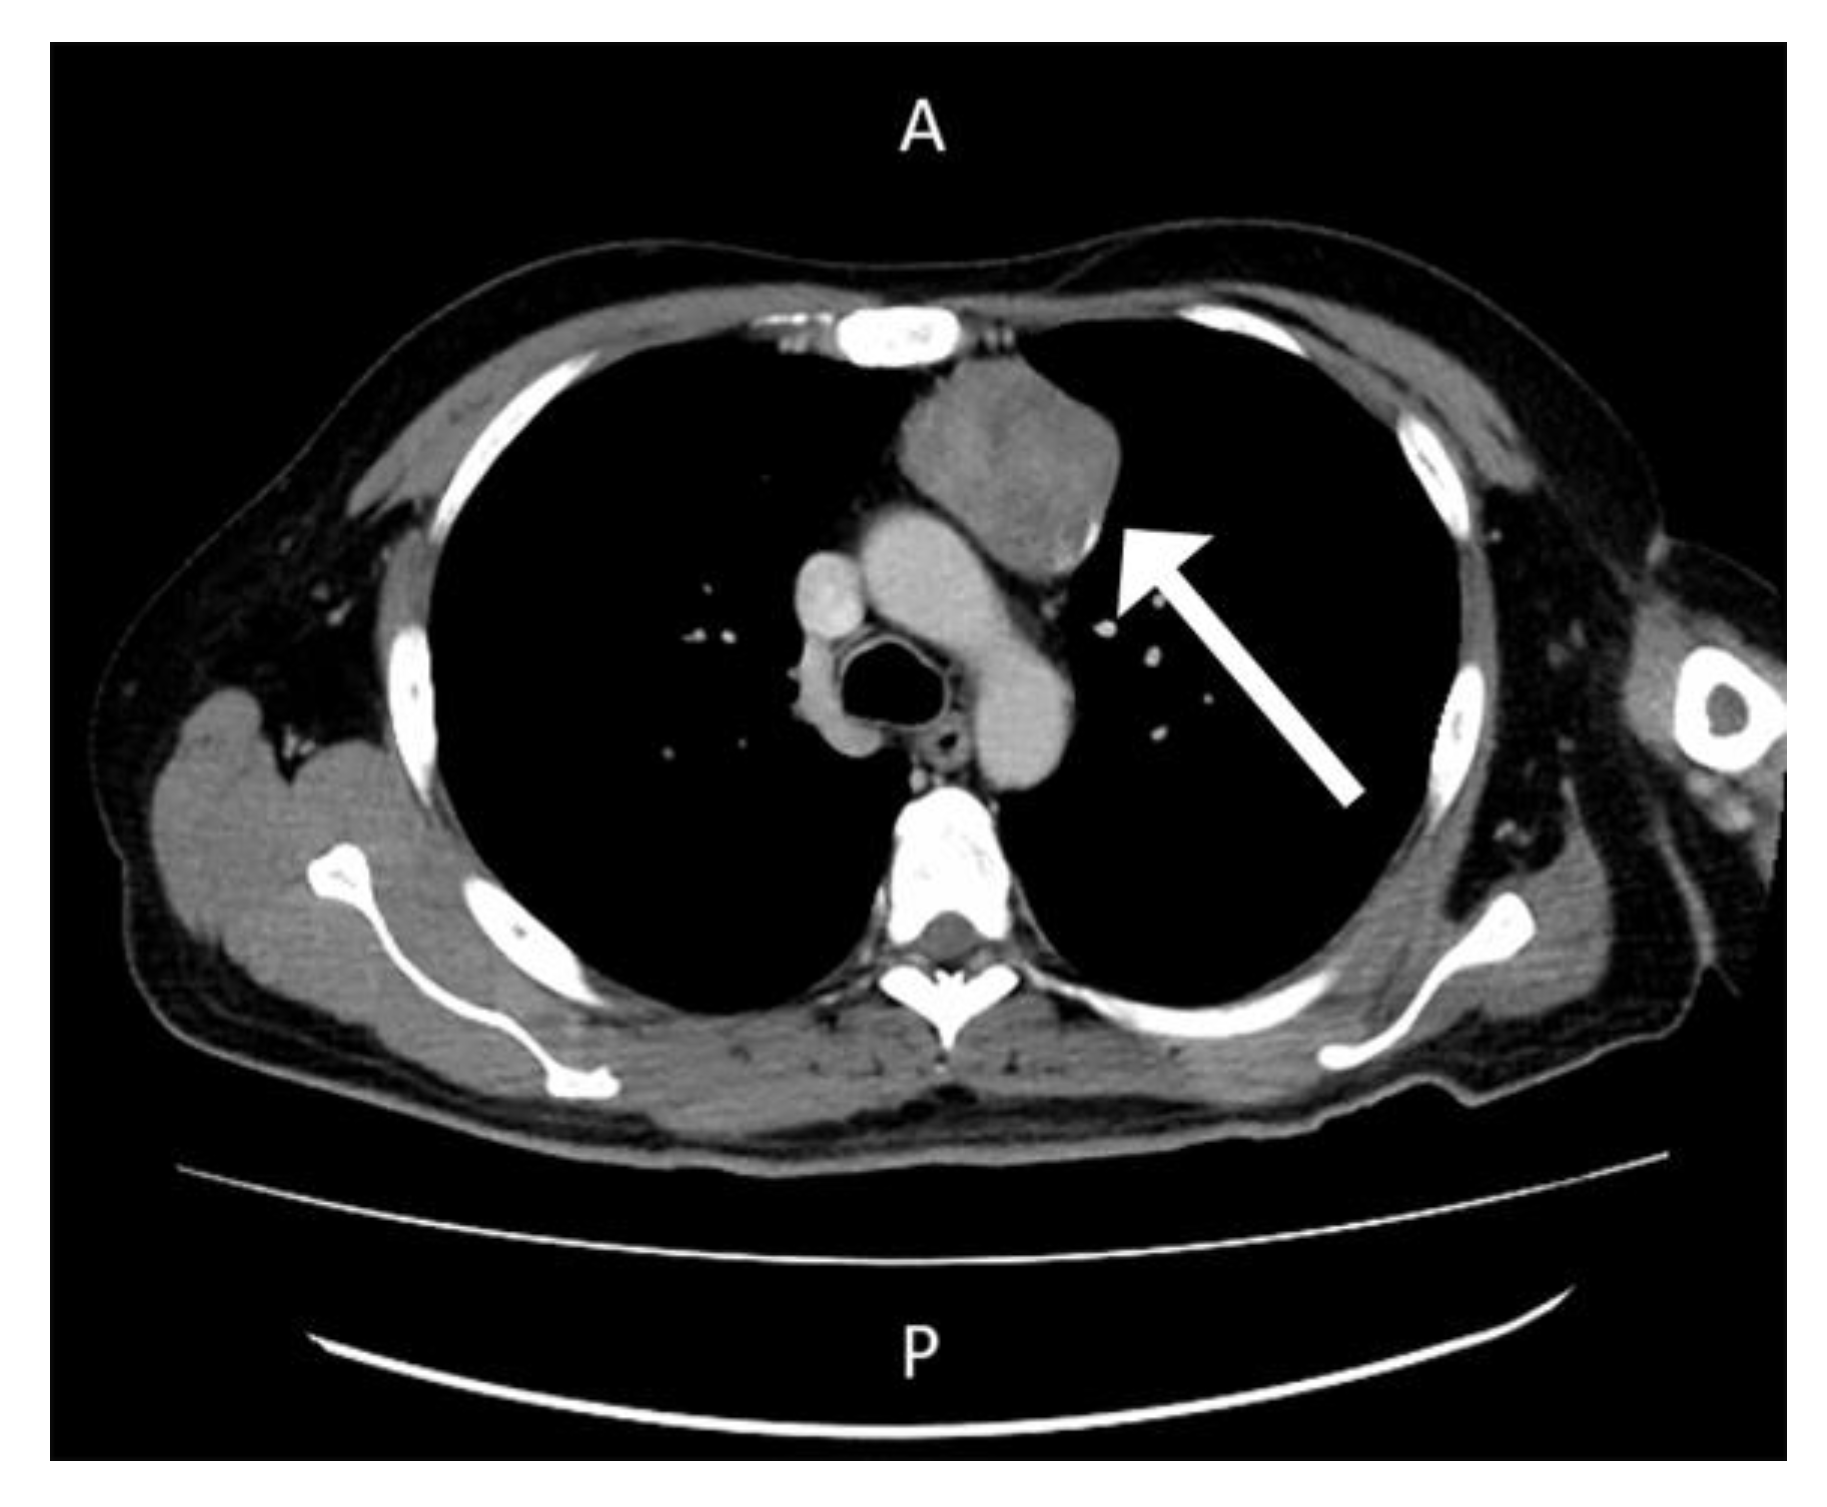

His first admission was to the division of infectious diseases. The 2019 novel coronavirus disease (COVID-19) had been excluded after repeated blood sampling and plain X-ray films of the chest. Blood tests showed a white blood cell count of 12,850 cells/mm3, hemoglobin level of 13.3 g/dL, platelet count of 490,000 cells/mm3, plasma creatinine level of 1.0 mg/dL, alanine aminotransferase (ALT) level of 79 U/L, aspartate aminotransferase (AST) level of 38 U/L, and c-reactive protein (CRP) level of 15.00 mg/L. Serum tests did not identify viral hepatitis infection. Microbiology examination of the sputum, blood, urine, and feces did not identify any pathogens. Blood sampling did not detect any autoantibodies. Physical examination did not reveal abnormal murmurs of the heart or abnormal primitive neurologic reflexes. Plain X-ray films of the chest did not show mass lesions or abnormalities in the lungs. X-ray of the major joints of all limbs did not show fracture, erosion of bones, or abnormalities of soft tissue. A technetium-99m methylene diphosphonate bone scan revealed increased uptake in the left shoulder, elbow, wrist, and ankle, and right foot and toes, which was compatible with the clinically significant arthritis noted in the physical examination (Figure 1). The patient’s fever did not respond to antibiotics for 2 weeks from the first admission. Reactive arthritis was suspected initially because no significant pathogens or autoantibodies had been identified, and sterile inflammation was suspected. The fever responded to daily systemic methylprednisolone (40 mg), and the patient was discharged 17 days after the first admission.

Figure 1. A technetium-99m methylene diphosphonate bone scan revealed increased uptake in the left shoulder, elbow, wrist, and ankle, and right foot and toes.